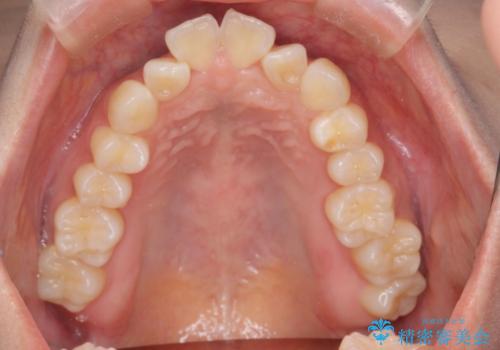

- 出っ歯、ガタツキ、噛み合わせが気になるとのことで来院された患者様です。

小臼歯を抜歯することでスペースを作り、前歯を下げて口元を下げ、Eラインを改善する治療方針としました。

表側のワイヤーは見た目が気になるとのことで、上の歯だけ裏側に付くハーフリンガルという装置で治療を行いました。